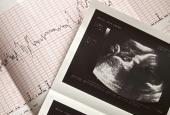

When pregnant, all of your attention goes to that one special day – the day your baby will be born. But that day comes and passes, and a few days later you need to go home to whatever you have prepared. You have plenty of time during pregnancy to plan everything you will need once you come home...

Preparing to Bring Your Baby Home